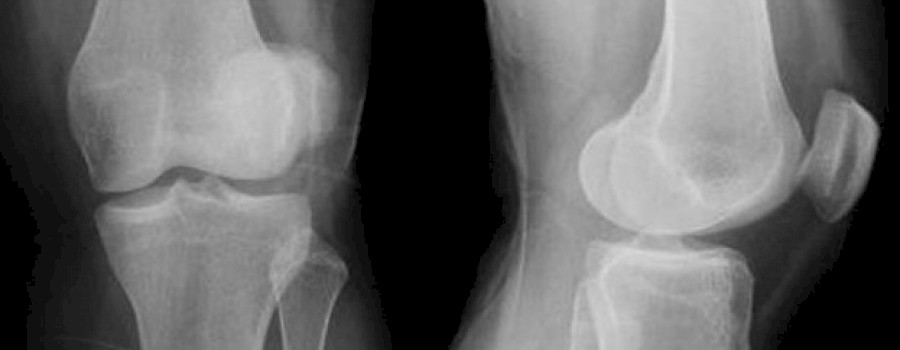

Patellarsehnenruptur

Die Patellarsehnenruptur ist ein Riss der Sehne zwischen dem unteren Pol der Kniescheibe (Patella) und dem Schienbeinhöcker (Tuberositas tibiae).